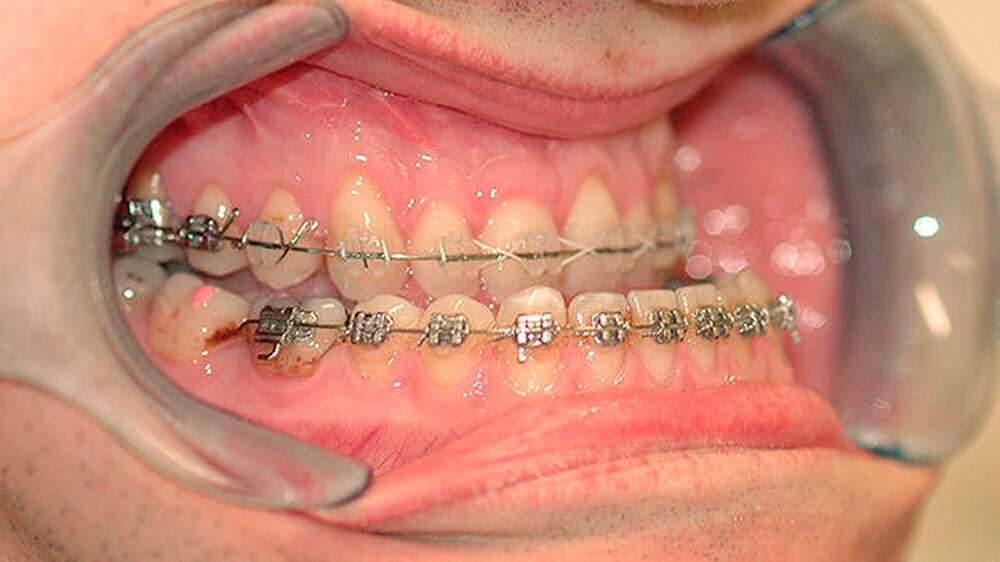

Der Patient stellte sich erstmals 2010 in der Stuttgarter MKG-Spezialsprechstunde vor. Im ersten Schritt wurde der Tumor an der Hirnanhangdrüse über die Nase entfernt. In interdisziplinärer Zusammenarbeit mit einem Fachzahnarzt für Kieferorthopädie wurden im ersten Behandlungsabschnitt die Zahnbögen ausgeformt. Um den Oberkiefer in der Breite zu dehnen, führten die Stuttgarter Zahnärzte im Oktober 2012 eine chirurgisch unterstützte Gaumennahterweiterung durch.

Nach dreidimensionaler Planung im zahntechnischen Labor, in dem die Bissschlüssel konventionell hergestellt wurden, wurden dann ein Jahr später beide Kiefer operativ mobilisiert. Hierzu wurde von einem Schnitt im Mund der Oberkieferknochen freigelegt.

Mit einer Säge wurde ein gezielter Knochenschnitt durchgeführt. Nach der Präparation wurde der zahntragende Abschnitt des Oberkiefers vom restlichen Gesichtsschädel gelöst. Erst wurde die Bisssituation anhand des Bissschlüssels exakt eingestellt, dann mit 2 mm dicken Osteosyntheseplatten aus Titan der Knochen in der neuen Position mithilfe von Titanschrauben fixiert.

Im Unterkiefer erfolgte dann die Schnittführung im Zahnfleisch hinter dem letzten Backenzahn beidseits. Nun wurde der Unterkiefer mit spezieller Technik durchtrennt um die zahntragende Basis vom gelenktragenden Knochenabschnitt des Unterkiefers zu verschieben. Bei der Präparationwurde der im Unterkieferknochen verlaufende Gefühlsnerv der Unterlippe sorgfältig geschont.

Die neue Position wurde mit einem zweiten Bissschlüssel, der die endgültige Bisssituation einstellt,zugeordnet und mit Osteosyntheseplatten und -schrauben gesichert. Die Operation ging mit einem stationären Aufenthalt von nur fünf Tagen einher.